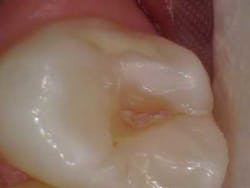

3 canals! Courtesy of Dr. Joe Petrino, DDS